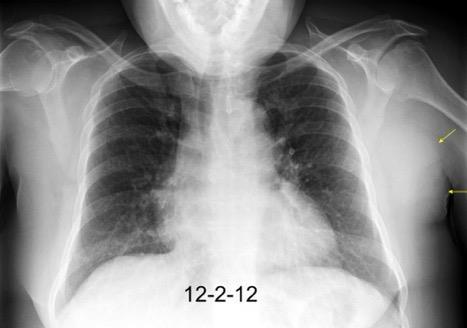

Pliegue axilar Normal

Rehúsa cirugía

2011. Acude por masa axilar

Linfoma NH de cél. B. Invasión Transtorácica.

Afectación axilar